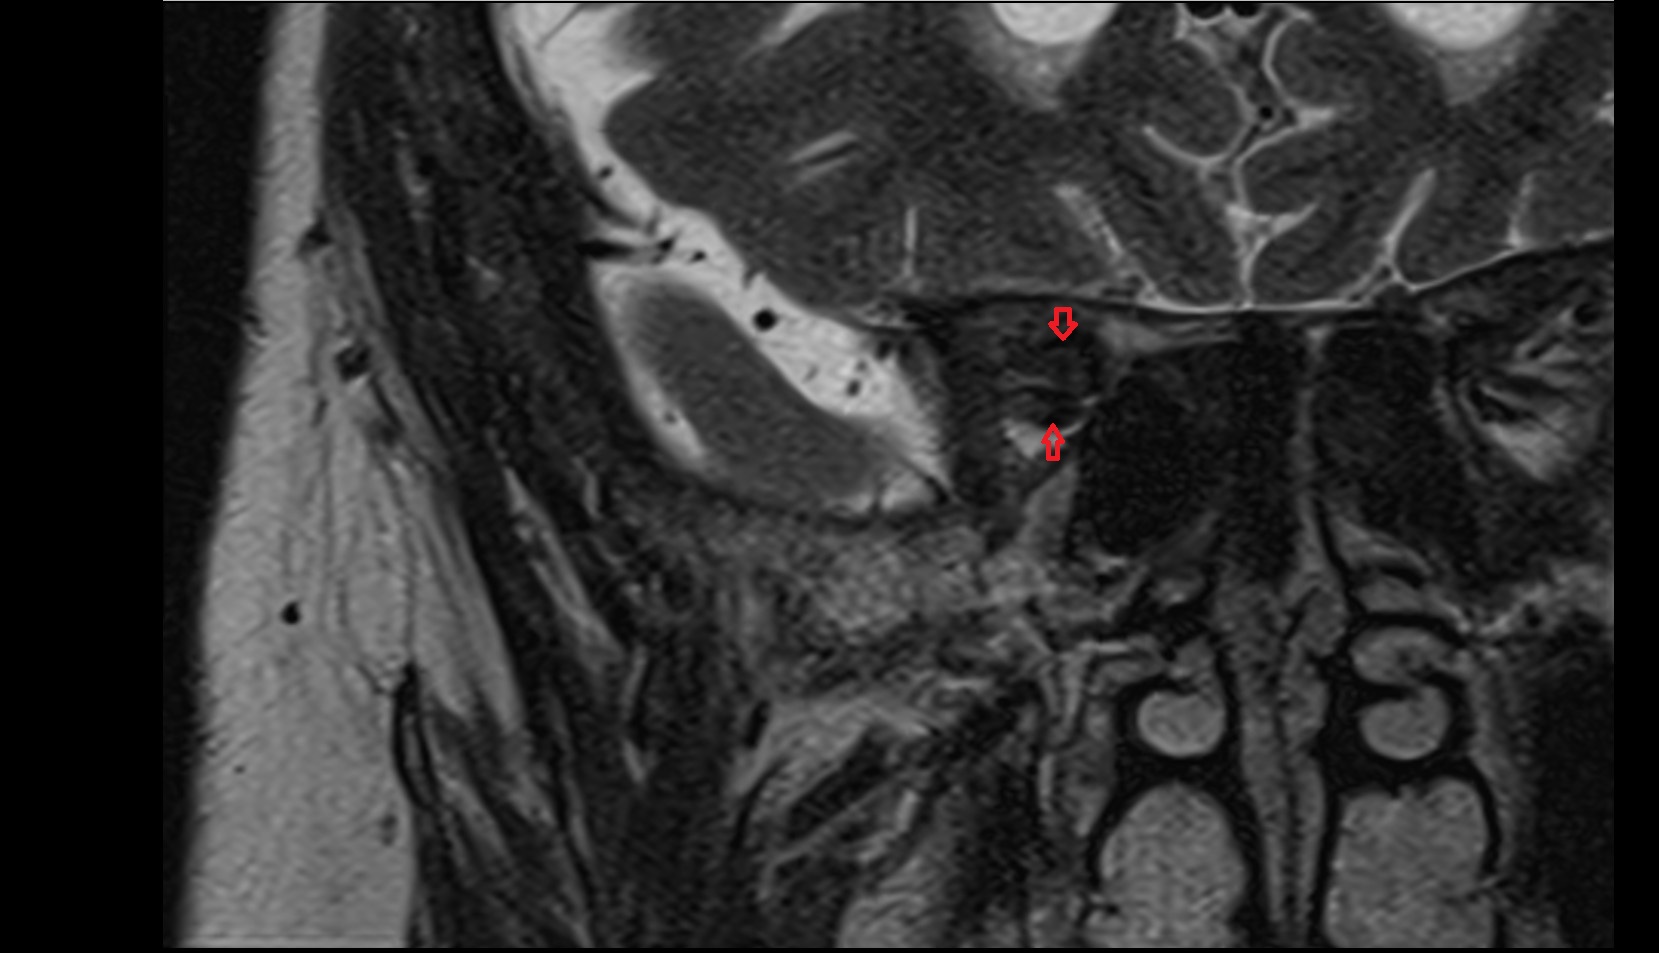

- Temporomandibular joint

- Mandibular condyle

- Mandibular fossa

- Articular disc of temporomandibular joint

- Articular eminence